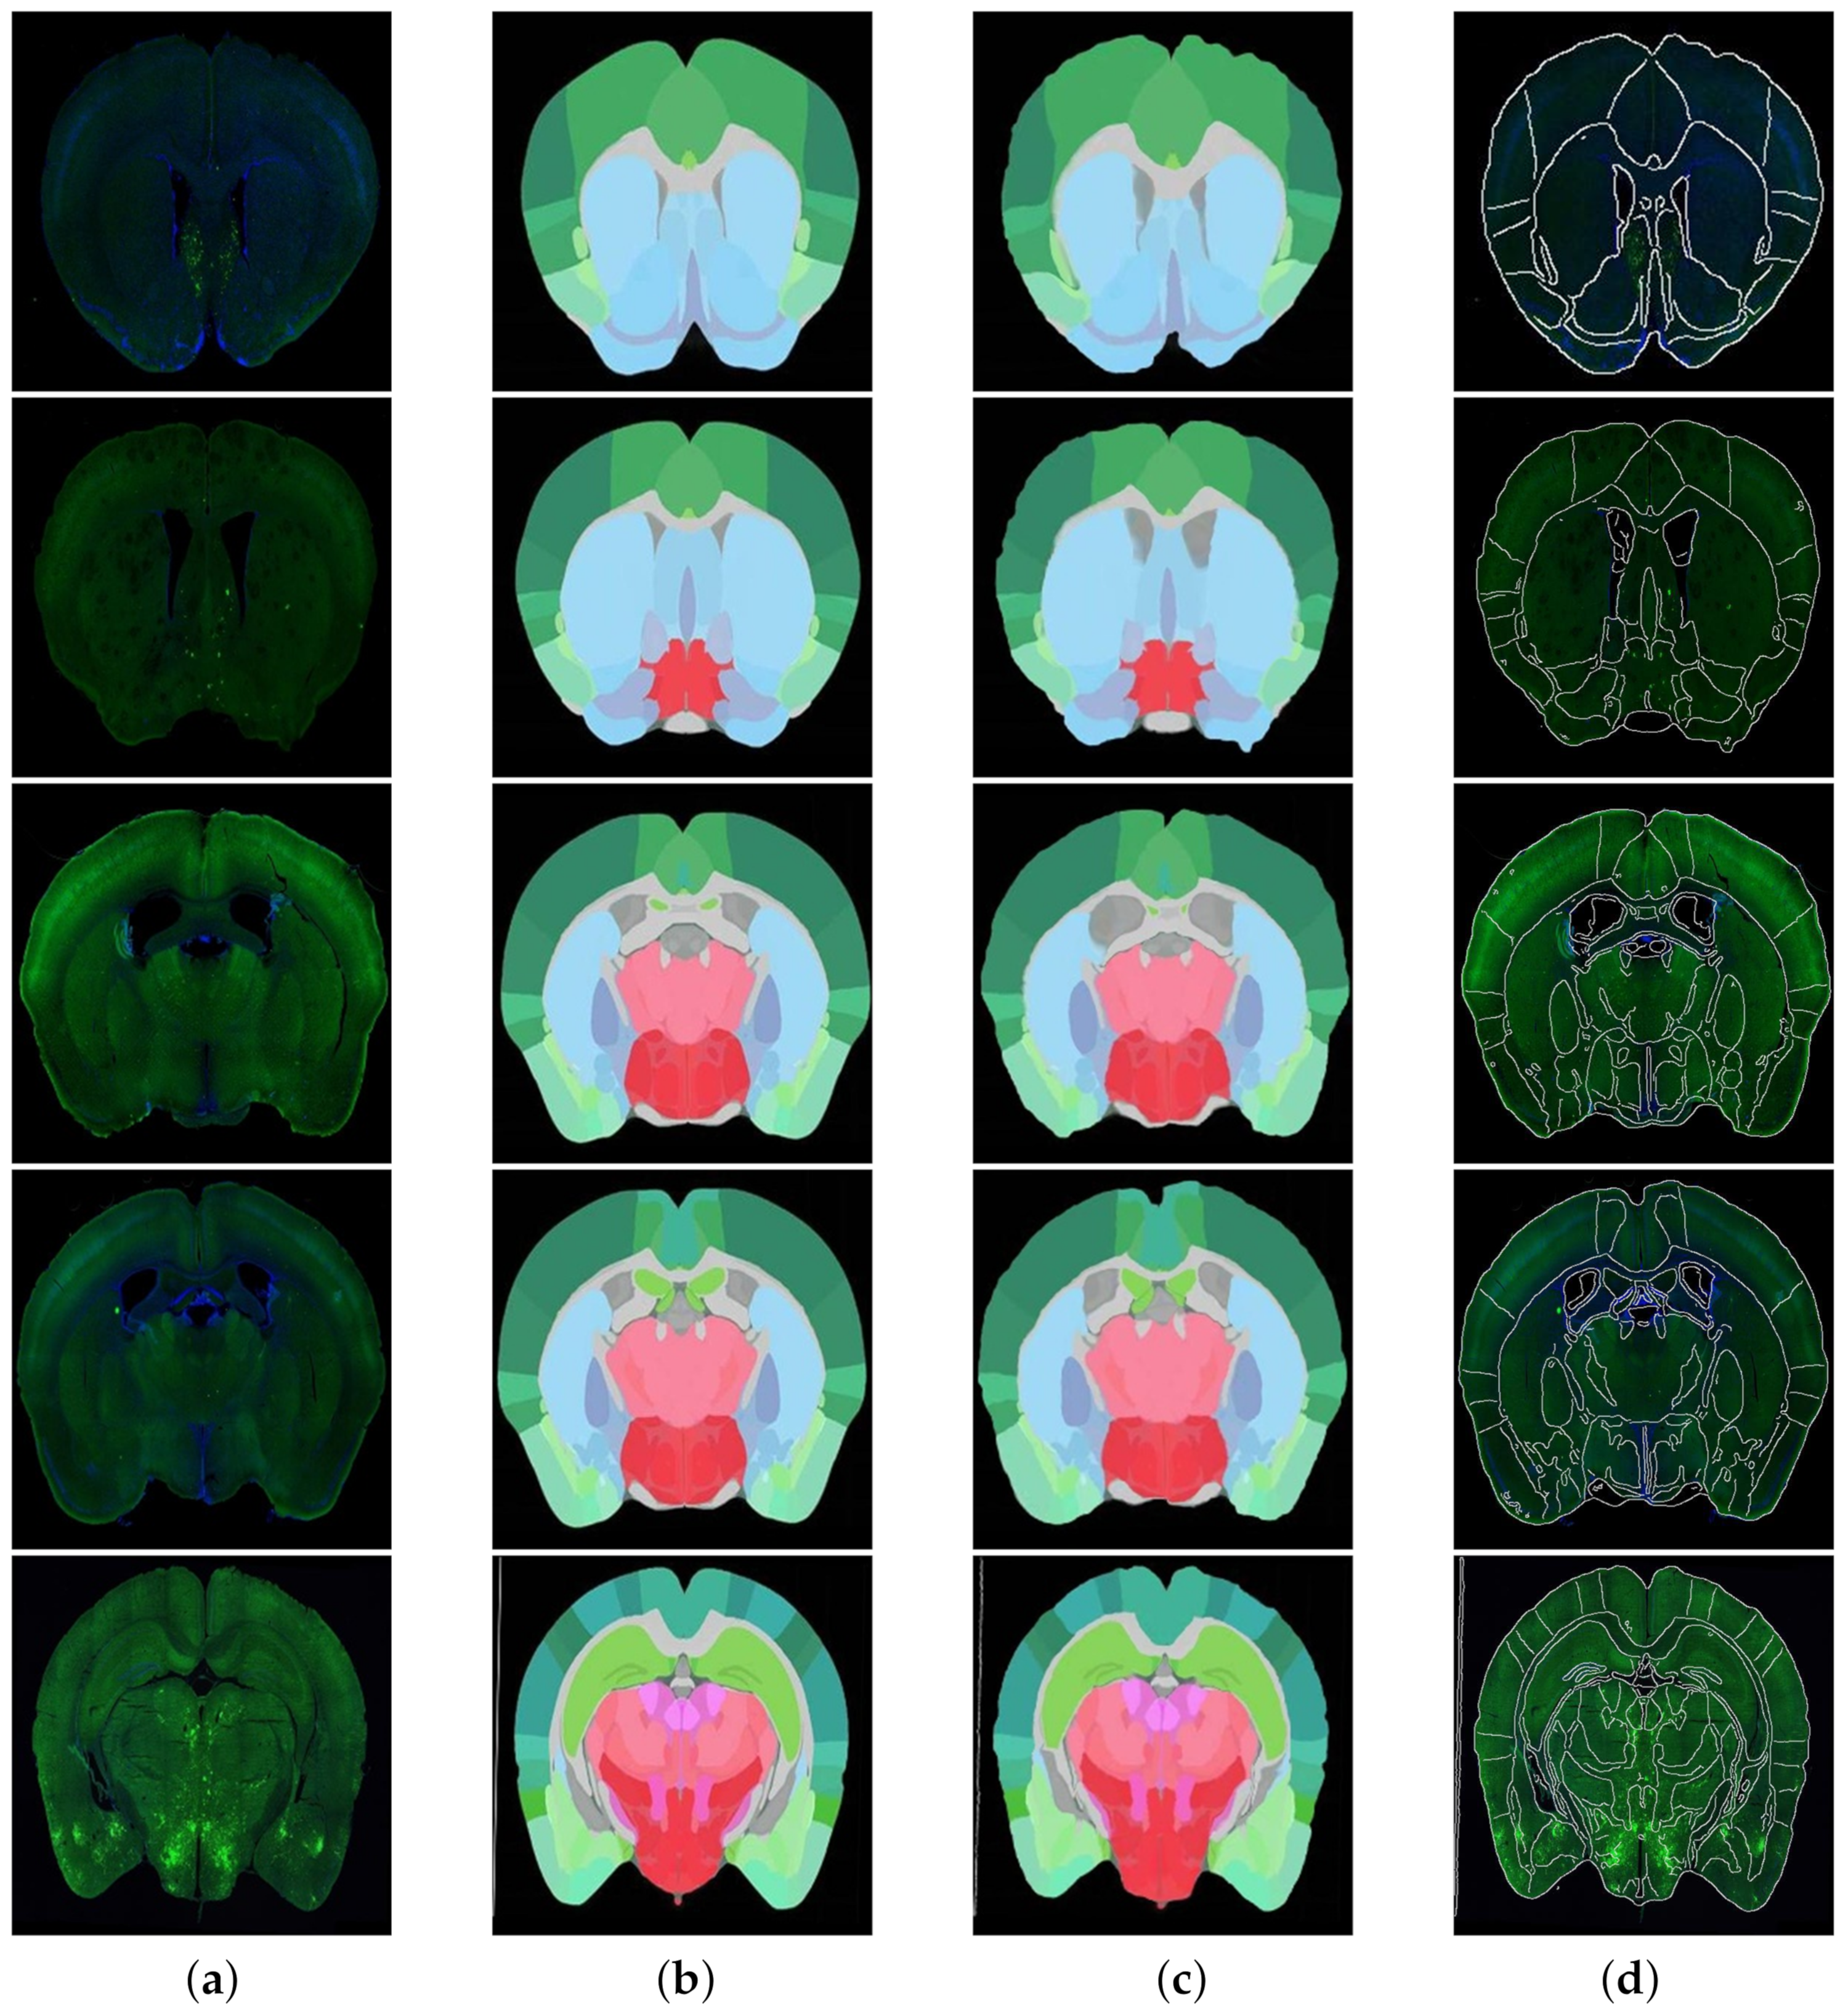

According to the fusion effect of images, the results of the regional localization method in this study were noticeably better than others. The external edge and internal feature contour fit well with the brain slice images, and the original topological structure was left unchanged. The regional localization effect of some brain slices is shown in Figure 12.

Figure 12. Five examples of regional localization of the brain slice. (a) is the original brain slice; (b,c) represent the ADA and its deformation after registration, and (d) shows the fusion of the edge contour of (c) and the image of (a).